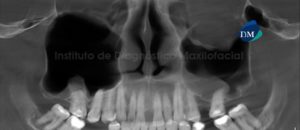

Paciente masculino de 55 años de edad que es referido para el estudio imagenológico a consecuencia de un leve dolor a nivel del maxilar superior